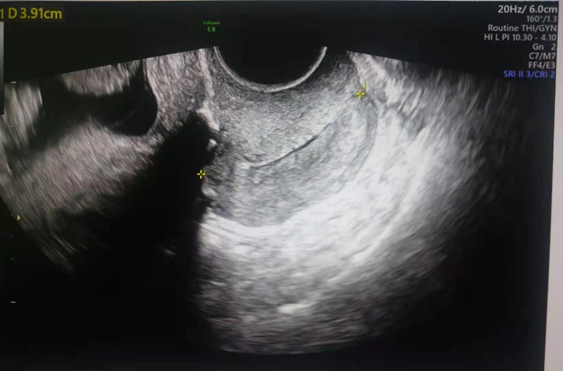

Patient was discharged from the hospital 15 days after the procedure at 25weeks 1day gestation age. Patient was advised to stay longer in the hospital but declined. On the day of discharge, she had no complaints, her physical examination, fetal assessment and ultrasound findings were normal with closed cervical os and cervical length as shown in Figure 4. One day after discharge, patient returned back to our hospital for readmission with complaint of lower abdominal pain which started 2 hours prior to presentation. She had no other complaints. Vaginal examination revealed a loose cervical cerclage tape and protruding unruptured amniotic sac membranes. Other physical examination findings were normal. Patient underwent a second transvaginal cerclage placement (Shirodkar procedure) successfully with the continuation of antibiotics, tocolytic medication, magnesium sulphate and progesterone. Six days after readmission, patient went into spontaneous labor and the cervical cerclage was removed to ease progress of normal labor. Spontaneous vaginal delivery of male infant of 940g, Apgar score of 3, 7, 9 at 1, 5, 10 minutes respectively was achieved. The neonate was admitted to the neonatal intensive care unit for prematurity. Mother was discharged from the obstetric ward 4 days after spontaneous vaginal delivery. The neonate was admitted in the neonatal intensive care unit for 79 days after which he was discharged at 2.16kg.

Figure 4 Showing closed cervical os, cervical length 3.91cm after transvaginal cerclage placement, (yellow asterisks).